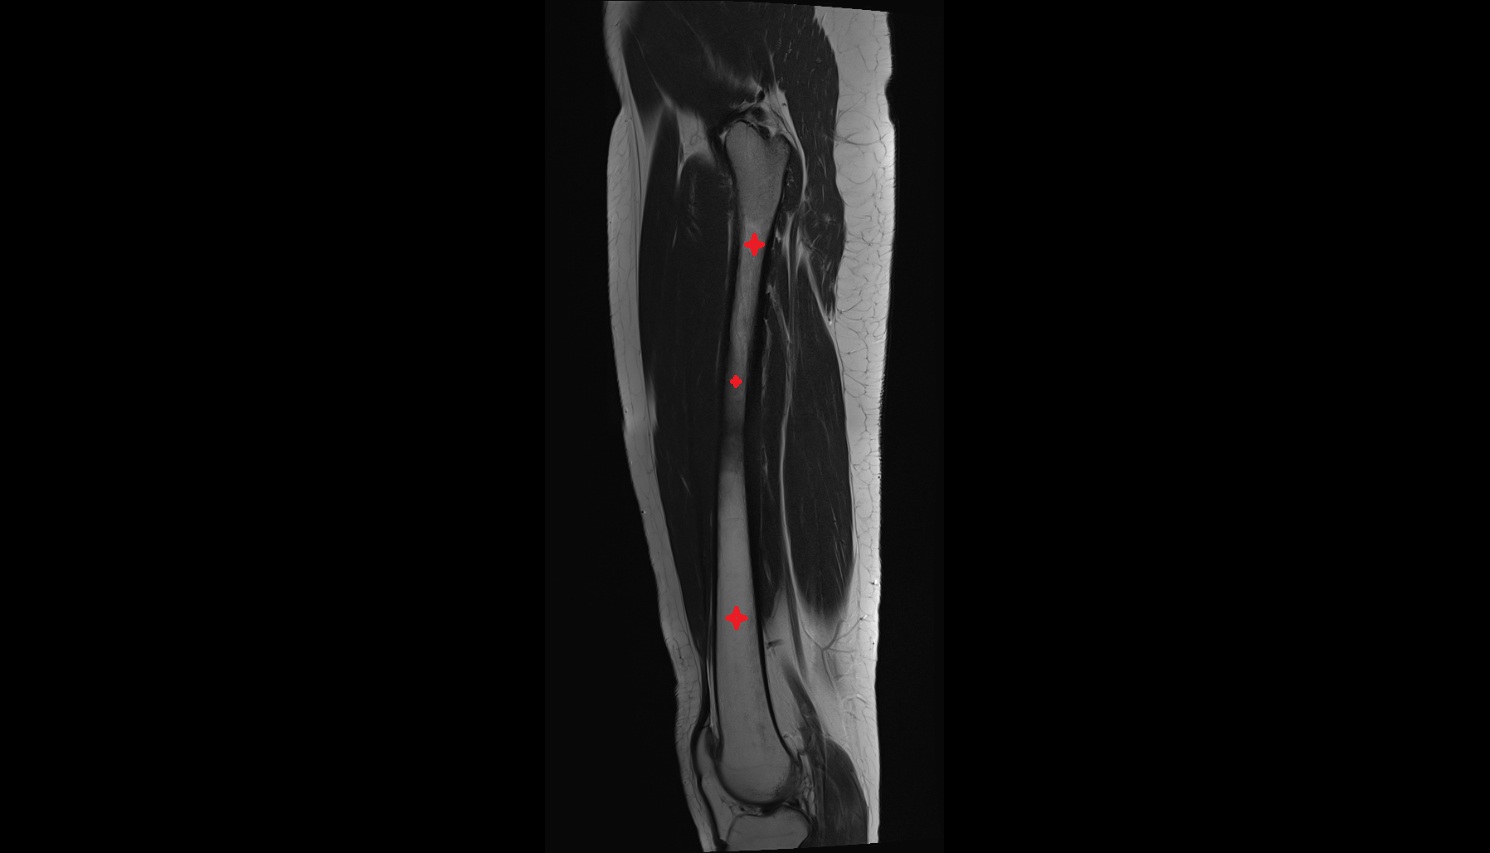

- Femur

- Femoral shaft

- Body of femur

- Semitendinosus muscle

- Semimembranosus muscle

- Biceps femoris muscle (Long head)

- Biceps femoris muscle (Short head)